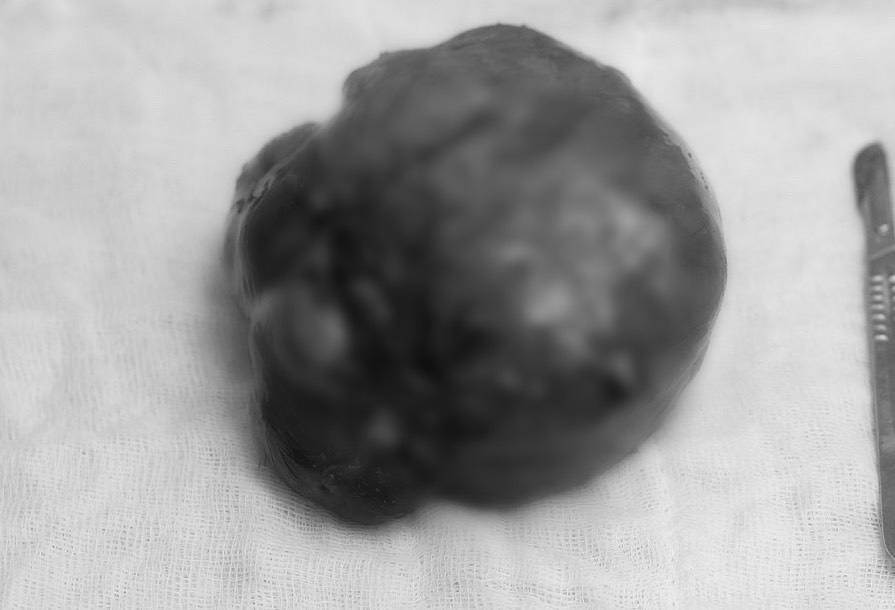

I operationssalen tog teamet bort tumören, avlägsnade sammanväxningar från tjocktarmen och tunntarmen, samt avlägsnade sammanväxningar vid urinledaren och urinblåsan. Sedan samarbetade de för att avlägsna och helt avlägsna den stora extraperitoneala tumören som mätte 20x30 cm, och slutligen utförde de en partiell hysterektomi. Efter cirka 3 timmar var operationen framgångsrik. Efter operationen kunde patienten urinera normalt.

Stor fibroid tumör